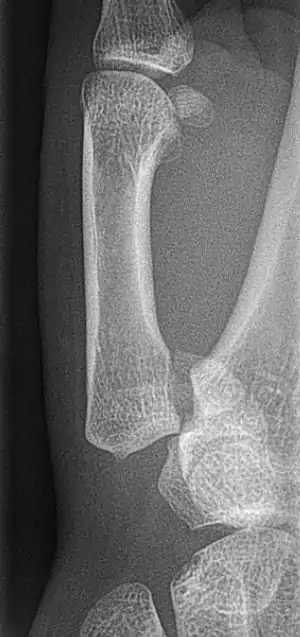

Bennett fracture is a fracture of the base of the first metacarpal bone which extends into the carpometacarpal (CMC) joint.[1] This intra-articular fracture is the most common type of fracture of the thumb, and is nearly always accompanied by some degree of subluxation or frank dislocation of the carpometacarpal joint.

In the case of the Bennett fracture, the proximal metacarpal fragment remains attached to the anterior oblique ligament, which in turn is attached to the tubercle of the trapezium bone of the CMC joint. This ligamentous attachment ensures that the proximal fragment remains in its correct anatomical position.

The distal fragment of the first metacarpal bone possesses the majority of the articular surface of the first CMC joint. Unlike the proximal fracture fragment, strong ligaments and muscle tendons of the hand tend to pull this fragment out of its correct anatomical position.